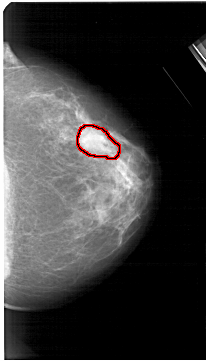

A_1533_1.LEFT_MLO

LEFT_MLO LINES 5311 PIXELS_PER_LINE 3151 BITS_PER_PIXEL 12 RESOLUTION 43.5 NON_OVERLAY

FILE: A_1533_1.RIGHT_MLO.OVERLAY

TOTAL_ABNORMALITIES 1

ABNORMALITY 1

LESION_TYPE MASS SHAPE IRREGULAR MARGINS ILL_DEFINED

ASSESSMENT 4

SUBTLETY 3

PATHOLOGY MALIGNANT

TOTAL_OUTLINES 1

BOUNDARY